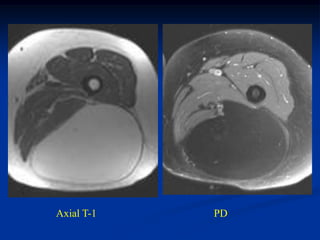

Case #298.1   Hemangioma Ankle                Sag Gad

Case #298.1

15 year male with tender

mass lateral side of forefoot

for many years

Axial T-1

T-2

Hemangioma Case #298.1 15 yearmale with tender mass lateral side of forefoot for many years